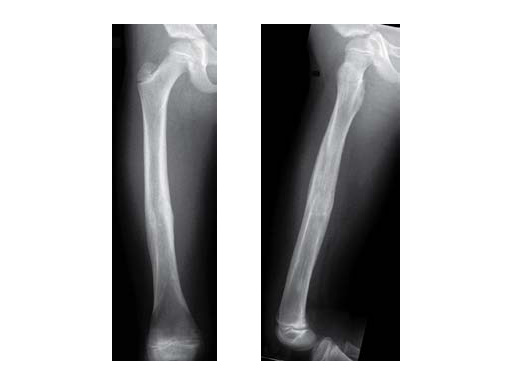

12-year-old boy; snow-board injury long spiral proximal femoral fracture (32D/5.1) primary indication for operation with ESIN and End Cap.

ab

Injury x-rays.